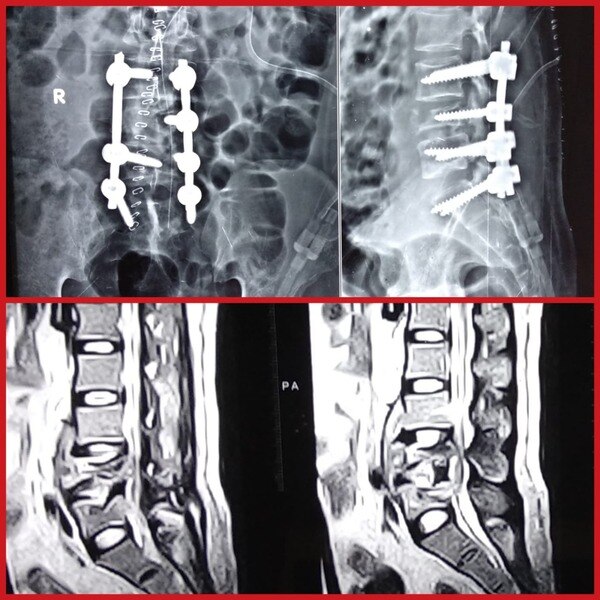

Dr. Rahul Chaudhari is a Reliable and Best Spine Surgeon, Spine Doctor, Spine Specialist in Bavdhan, Pashan, Sus, Bhugaon and Pune. Dr. Rahul Chaudhari is the USA trained Orthopaedic Spine Surgeon in Pune. He completed his MBBS/MS from KEM Hospital, Mumbai. He had received advanced spine/scoliosis surgery training in America for 3 years. His expertise involves treating cervical, thoracic, and lumbar spine disorders including degenerative spine conditions (slipped disc, sciatica, and spinal stenosis), fractures, tumors, and spinal deformities. He successfully treated many happy patients in his 17 years of journey as an Orthopedist.